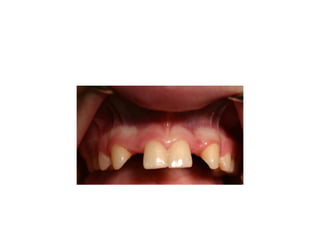

Missing maxillary incisors

• Missing teeth, because of trauma or congenital

absence, generally affect the maxillary anterior

region. Aesthetic improvement is the real desire

of the patient. Treatment solutions include

orthodontic space closure, auto-transplantation

orprostheticreplacement(bondedorfixeddental

bridges, or implant-supported crowns). All

alternatives have their advantages as well as

disadvantagesandproperdecisionsshouldbemade

already in young ages.